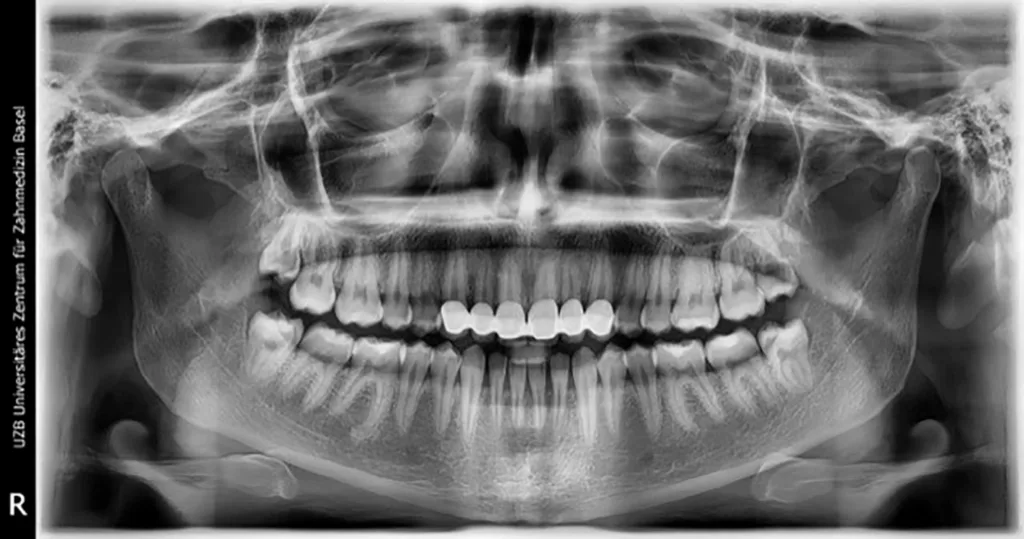

Röntgenologischer Befund

Das OPT (Abb. 1a) gibt keinen Anhalt auf nicht zahnverursachte Prozesse, alle vier Weisheitszähne sind vorhanden und retiniert. Die Bissflügelaufnahmen (Abb. 1b und c) zeigen insuffiziente konservierende Versorgungen an den Zähnen 26, 36, 37 und 46 sowie okklusale Karies an Zahn 16.